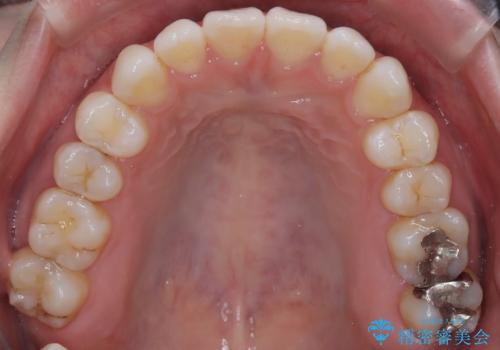

【インビザライン】がたつきをなおしたい

- 上下の前歯の凸凹が気になり、来院されました。

インビザラインで綺麗に仕上がり、満足していただきました。